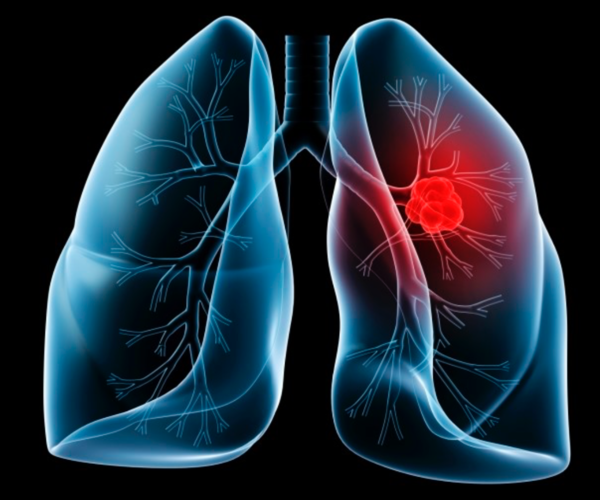

폐암은 암 사망률 1위이면서, 발생도 4위일 정도로 병이 나서율이 높은 암이면서 조기 발견이 어렵습니다. 폐암은 소세포암과 비소세포암으로 나뉘는데 소세포암은 전이가빠르고 악성 정도가 높아 무서운 암이라고 할 수 있습니다.

폐암의 종류

1) 비소세포암

비소세포암은 폐암 전체의 약 70% 입수할리만큼 대개 비소세포암이 생겨나게 돼요. 비소세포암은 편평상피암, 선암, 대세포암으로 나누어져요.

2) 소세포암

폐암가운데 15~20%는 소세포폐암으로 악성도가 높은 암이희망하더라고요. 소세포암은 발견 당시 이미 림프관, 혈관을 통해 다른장기나 반대편폐, 종격, 심장, 기관, 식도, 대동맥 등으로 전이되는 경우가 많으므로서 치료 후 경과가 굉장히 좋지않은 암이에요.